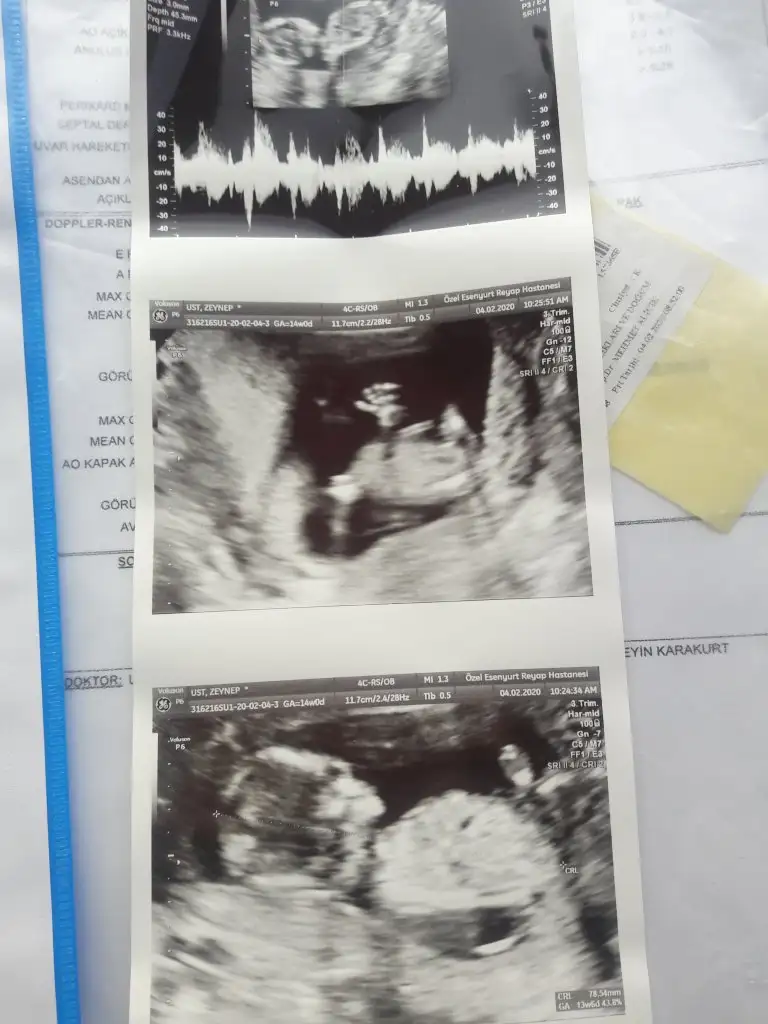

• 20200204_105219.webp

20200204_105219.webp

39,8 KB · Görüntüleme: 48

Bence erkek bebek